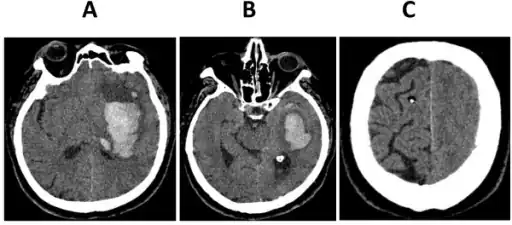

a-c)CT scan images after clinical signs of brain herniation developed

Types of brain herniation.[6]